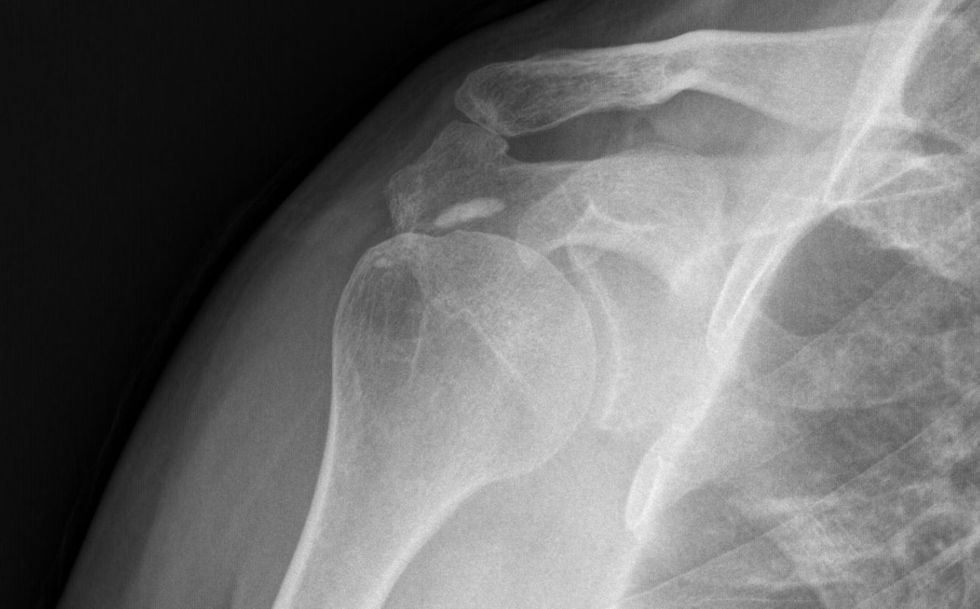

Kalcifikimet e shpatullave, të njohura gjithashtu si tendiniti i kalcifikuar, ndodhin kur depozitat e kalciumit grumbullohen në tendinat e shpatullës. Kalciumi shkakton acarim të tendinave të manshetës rrotulluese, gjë që mund të çojë në dhimbje akute. Zakonisht ndodhin në supraspinatus, megjithëse mund të ndodhin edhe në tendinën infraspinatus ose subscapularis.

Është i mundur edhe tendiniti asimptomatik kalcifikues, i cili zbulohet rastësisht gjatë ekzaminimit radiografik edhe përgjatë diagnostikimit të ndonjë patologjie tjetër.